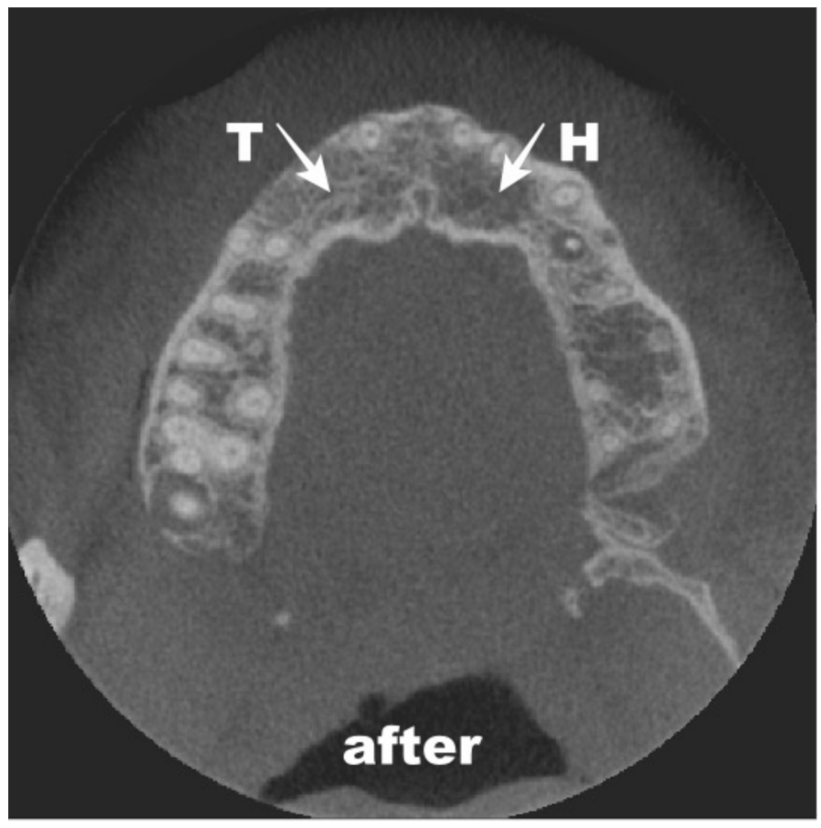

3. Materials and Methods

4. Results